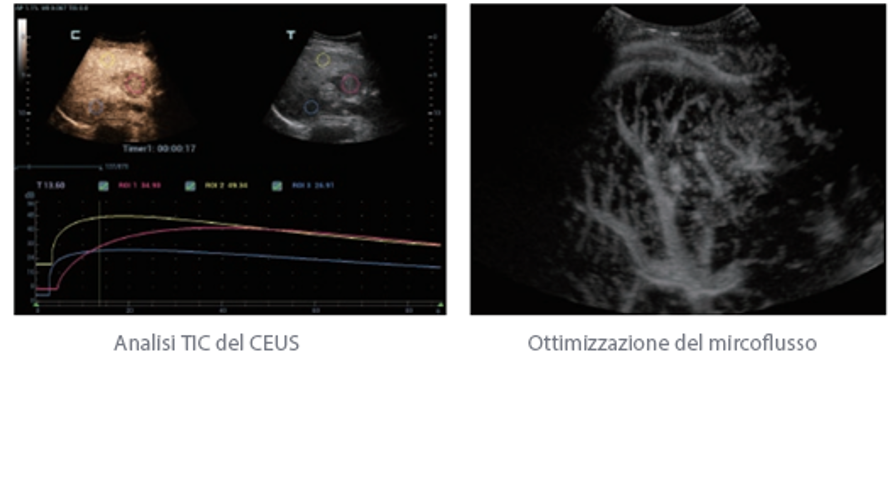

Oltre alla qualit├Ā delle immagini di livello eccellente, Resona 7 migliora anche le capacit├Ā di ricerca clinica il rivoluzionario V Flow per la valutazione emodinamica vascolare, e l'acquisizione piani pi├╣ intelligente dal set di dati 3D per la diagnosi del sistema nervoso centrale fetale. Combinando il pi├╣ intuitivo funzionamento multi-touch basato su gesti e tutte le caratteristiche cliniche essenziali, Resona 7 sta veramente portando nuove tendenze nellŌĆÖinnovazione dellŌĆÖecografia.